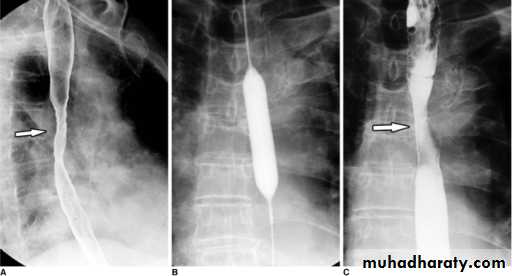

Dysphagia is defined as difficulty in swallowing.

Dysphagia can occur due to problems in the oropharynx or esophagus.

Oropharyngeal disorders affect the initiation of swallowing at the pharynx and upper esophageal sphincter.The patient has difficulty initiating swallowing and complains of choking, nasal regurgitation or tracheal aspiration. Drooling, dysarthria, hoarseness and cranial nerve or other neurological signs may be present.

Esophageal dysphagia disorders cause dysphagia by obstructing the lumen or by affecting motility. Patients with esophageal disease complain of food ‘sticking’ after swallowing.